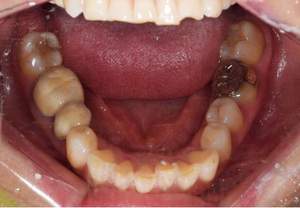

治療前

治療後

| 治療内容 | 右下6番・右上6番・左上6番フルメタルクラウン 除去、仮歯作成、 ジルコニアステイン形成、 右上6番・左上6番コア形成 |

| 治療費 | 合計 372,900円(2022年10月現在) ジルコニアステイン 110,000円×3本 仮歯 3,300円×3本 ファイバーコア 16,500円×2本 |

| 治療期間 | 3ヶ月 |

| 治療のリスク・副作用 | 仮歯の期間は仮歯が取れやすくなっている。 天然歯より硬いので噛み合う歯が欠けてしまうことがある。 |

| 特記事項 | 右上6番、左上6番に関しては根管治療が必要になる。 |